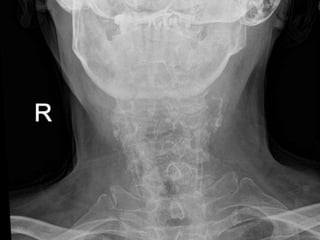

69 year old man with C2

fracture

Admitted for CHF and while

hospitalized was walking to

the bathroom at night and

fell on to head lacerating

forehead. Staff responded

to his calls for help and

immediately ordered a

cervical CT due to

complaints of new neck

pain

PMH: COPD, CHF,

anxiety/dep, liver cirrhosis,

cognitive decline,

pulmonary HTN,

SH: retired lives in group

home

69 year oldman with C2 fracture Admitted for CHF and while hospitalized was walking to the bathroom at night and fell on to head lacerating forehead. Staff responded to his calls for help and immediately ordered a cervical CT due to complaints of new neck pain PMH: COPD, CHF, anxiety/dep, liver cirrhosis, cognitive decline, pulmonary HTN, SH: retired lives in group home